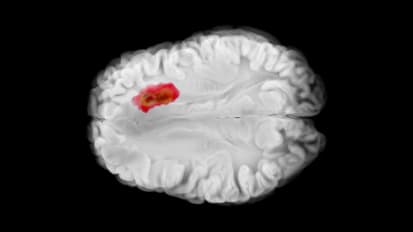

HIFU is an FDA-approved procedure that uses highly focused ultrasound waves to target a small area in the brain’s thalamus responsible for tremors.

Eliminating Tremor with HIFU: fast, effective, and non-invasive

Originally presented by Dr. Justin Sporrer on Tuesday, August 23rd at 6:00 PM. Participants will be able to, identify and review the diagnosis and treatments of various tremors and discuss focused ultrasound as a non-invasive treatment for tremors.